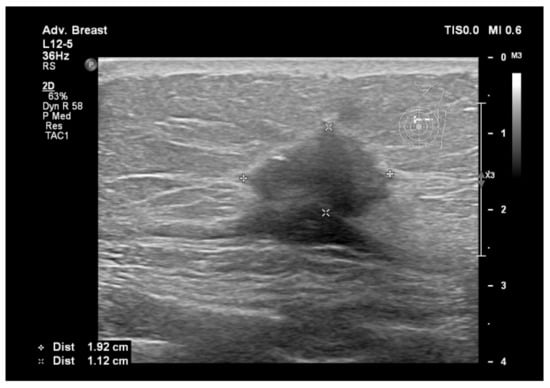

6.1. Characterization of Lesions

9. Types of Lesions Found by Screening with Breast Ultrasound